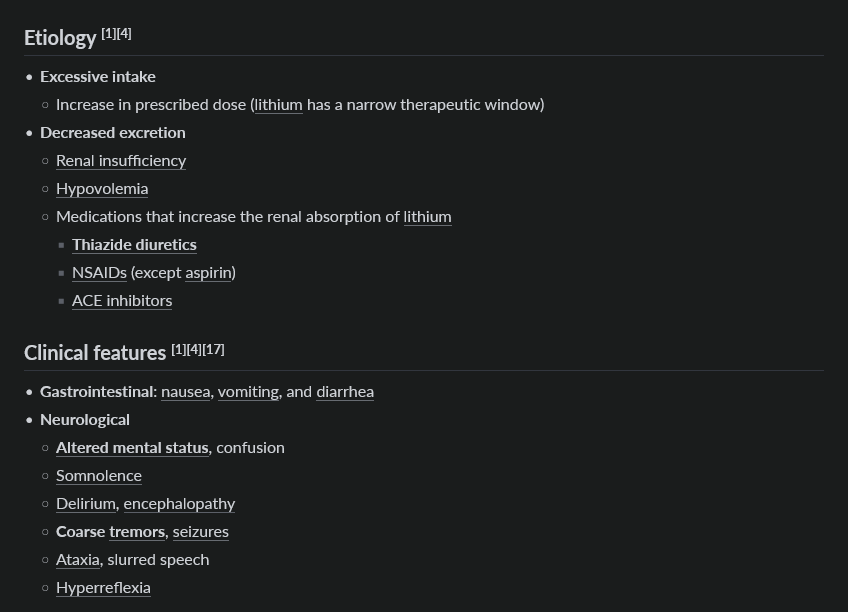

lithium tox

hemodialysis if AMS, seizures, or life-threatening arrhythmia